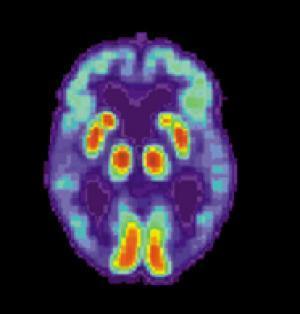

This second portion of the study will continue to define subtle changes that occur in the brains of older people, many years before clear signs of Alzheimer’s begins to appear. The study looks at pictures of the brain and measures of blood and spinal fluid.

Participants' brains will be examined for any changes, in constitution or function, as people transition from normal cognitive aging to mild cognitive impairment to Alzheimer’s dementia. By examining people who are at risk for the disease and tracking its progression, the researchers hope that they can determine possible interventions.